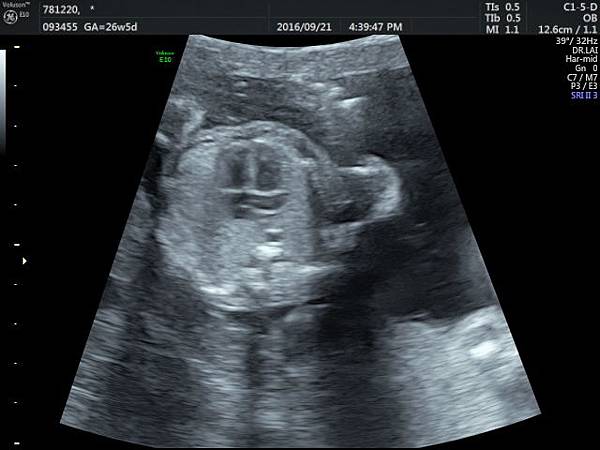

2016年9月21日幫一位懷孕26歲懷雙胞胎的孕婦看胎兒心臟超音波,孕婦目前26週,雙胞胎大小相差四週,高層次超音波除了小的胎兒臍動脈血流有問題之外,沒有其他異常發現,經過我的檢查,我的診斷是小的胎兒有持續性左側上腔靜脈(附圖1~5)。

正常情況左側的上腔靜脈在胚胎發育過程應該要退化,左側頭頸部的靜脈回流是流向右側的上腔靜脈再回到右心房,而持續性左側上腔靜脈是這條血管沒有退化繼續存在,它的血流一般會流入左心房背部的冠狀竇(coronary sinus)再經由冠狀竇回到右心房,因為最終都是回到右心房,理論上沒有什麼問題,只是為何它會不退化呢?是否有什麼因素造成它不退化這才是重點所在,所以做染色體基因檢查的理由就是找出是否有原因。

因為冠狀竇變大,超音波影像常被誤解為心房中隔缺損,兩者的預後差很多,鑑別診斷需要經驗,我常跟孕婦說,如果只給我10分鐘檢查一位胎兒,我會選擇看胎兒心臟,因為心臟就像一部車子的引擎,胎兒先天性心臟病常會合併染色體基因的問題,藉由心臟檢查,可以縮小範圍。

持續性左側上腔靜脈如果沒有合併其他異常,可以視為正常的變異,不需要任何治療,也不會有什麼特別問題,但是如何排除是否合併其他問題呢?我建議需要做染色體及基因晶片檢查,並且需要做高層次超音波排除其他器官是否異常。